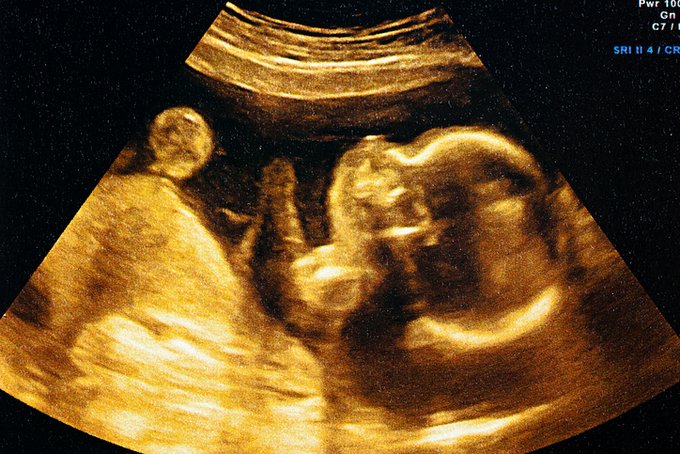

¿Estás embarazada o pensando en tener un hijo? Entérate sobre lo que puedes hacer para proteger tu salud y la de tu bebé contra defectos de nacimiento ow.ly/gryB50xPZrO #BirthDefectsPreventionMonth